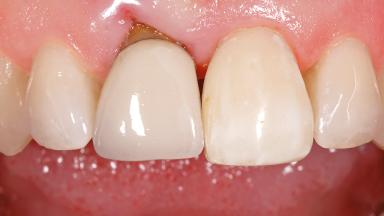

Early Placement of an Implant in a Maxillary Right Central Incisor Site

This 41-year-old female patient was referred to the clinic for the replacement of the right central incisor, since the tooth had developed a root fracture in the long axis that made extraction necessary. The healthy, non-smoking patient was first seen with the tooth still in place. A detailed Esthetic Risk Assessment was performed.The patient was worried about her dental esthetics and had high expectations for a successful treatment outcome from an esthetic point of view. The patient had a medium lip line that displayed parts of the gingiva in the anterior maxilla upon smile.

Lip Line No exposure of papillae Exposure of papillae Full exposure of mucosa margin

Periodontal Phenotype Low-scalloped, thick Medium-scalloped, medium-thick High-scalloped, thin

Shape of Tooth Crowns Rectangular Triangular

Soft Tissue Anatomy Intact Defective